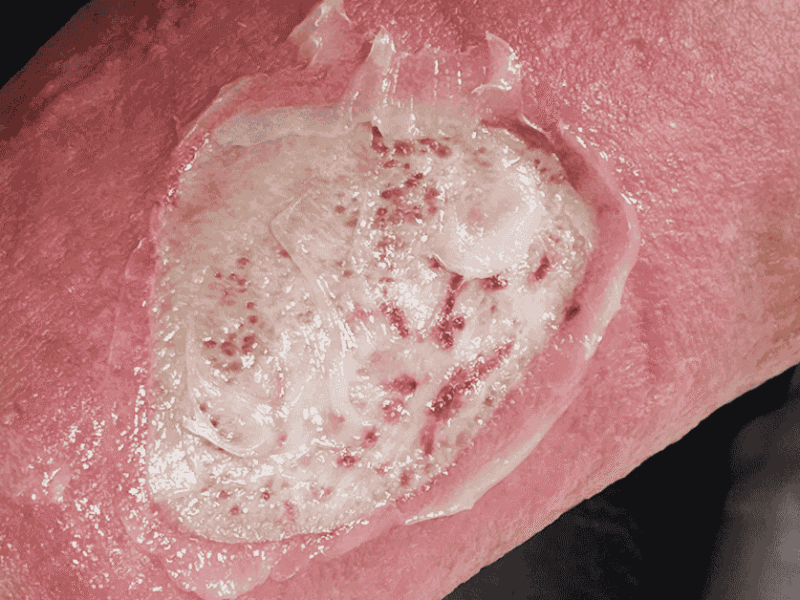

The Importance of Debridement in Wound Healing

When a wound fails to heal properly, one of the most common obstacles is the presence of dead or damaged tissue. This tissue can prevent healthy cells from regenerating and create an environment where bacteria thrive. To support proper healing, medical professionals often perform a procedure known as debridement. At Bellagio Wound Care, debridement is [...] Read More